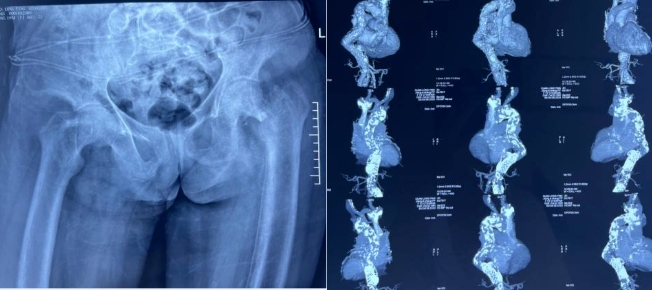

经过详细地询问病史以及体格检查,医生们得出较为复杂的病情诊断:左侧股骨颈骨折、腹主动脉夹层术后、胸主动脉继发夹层动脉瘤、尿毒症、血液透析(5年)、重度骨质疏松症、高血压病、肺气肿、支气管扩张、贫血。

10月11日,在李洪波团队及相关科室的通力配合下为该患者实施了左侧髋关节置换术,手术时间约30分钟,麻醉全程时间约60分钟,术后安全返回ICU。